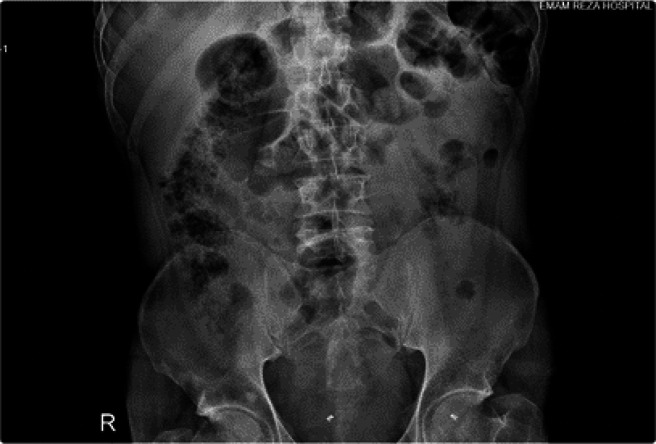

Malignant melanoma of the small intestine is mostly a metastatic tumor of other primary lesions, especially of skin origin. Primary malignant melanoma of the small intestine is very uncommon. The clinical presentation is usually nonspecific, thus leading to late diagnosis. We report a 42-year-old man who presented to the emergency department of Imam-Reza Hospital with symptoms and signs of peritonitis and was a candidate for emergency laparotomy and enterectomy. The medical and family history were unremarkable. A bulky mass was seen 190 cm away from the Treitz band, and a diagnosis of malignant melanoma was confirmed by histologic and immunohistochemical study. Further clinical examination revealed no primary tumor elsewhere, so the diagnosis of primary small intestinal melanoma was concluded. Although metastatic malignant melanoma in the GI tract is common, the primary one is a very rare entity. The diagnosis could be challenging because a thorough investigation is needed to rule out the possible initial origin.